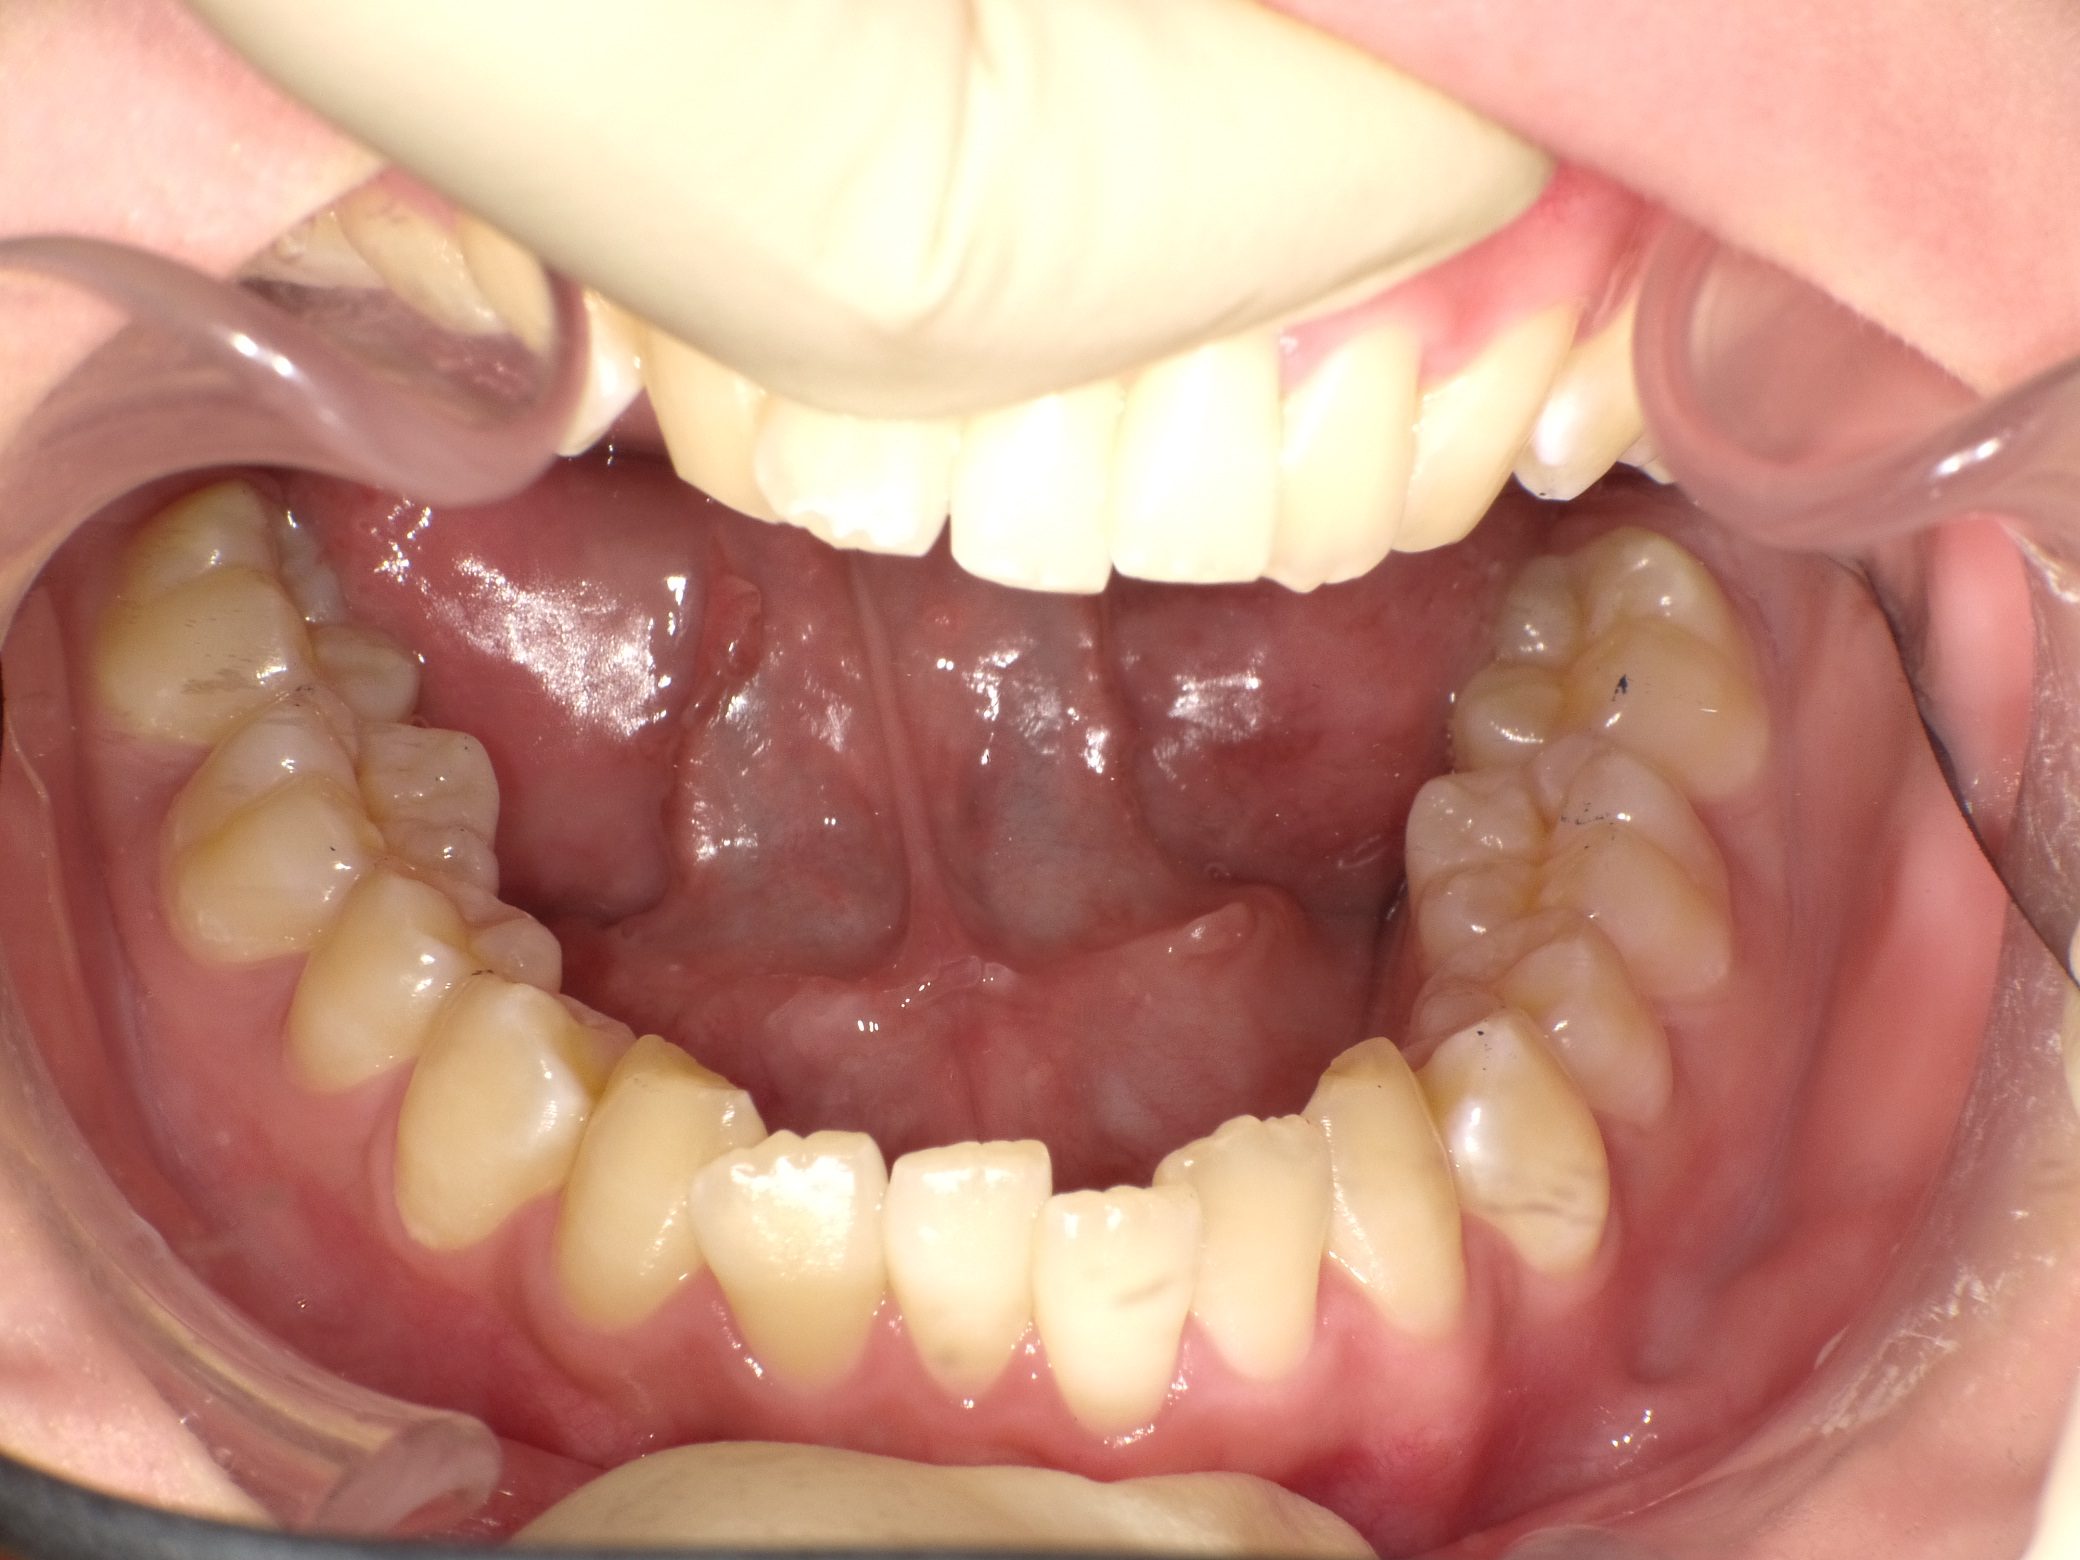

Before

After

【中学生】インビザライン矯正 叢生(ガタガタ)と上顎前突(出っ歯)を改善

でこぼこ

出っ歯

非抜歯

2期治療のみ

途中 留学などあり、装置(アライナー)を全部持って行ってもらう といった時期がありましたが、

装置(アライナー)が浮くこともなく しっかり進めてくれたので 1年4カ月で終了しました。